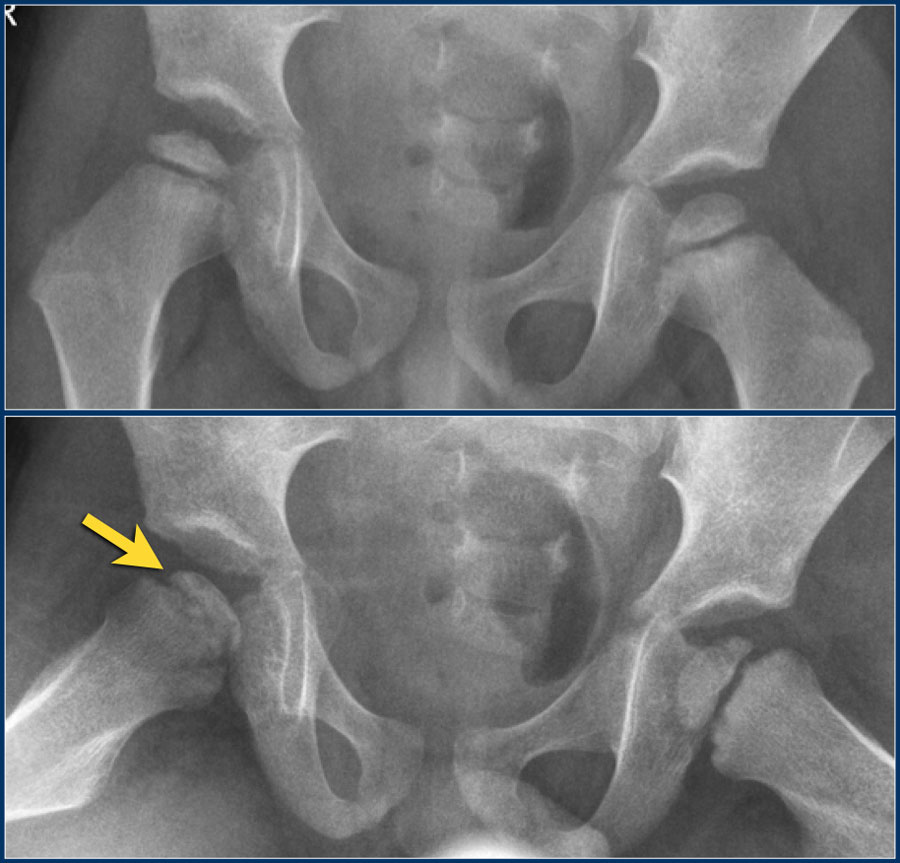

Рентгеновские снимки: Синовит тазобедренного сустава